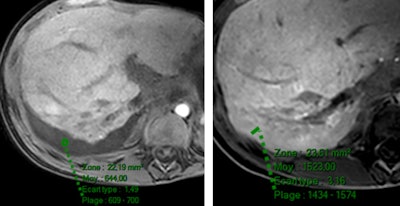

Two radiologist readers interpreted the scans qualitatively and quantitatively on precontrast, dynamic, and hepatobiliary phases. Qualitatively, fluid was described as hypointense in the hepatobiliary phase with Primovist, while it was hyperintense with MultiHance. When quantitatively measured, fluid signal intensity increased with both MultiHance and Primovist, but it was significantly more marked after MultiHance.

"Within the four groups we looked at what happened in the hepatobiliary phase. Nearly all the patients injected with MultiHance had iso- or hypersignal intensity of the fluid, but this was not true of those injected with Primovist," Ronot told AuntMinnieEurope.com ahead of the meeting.

"If you inject hepatospecific contrast agents there will be some degree of fluid enhancement but this is generally not seen with Primovist because the time from injection to image acquisition is too short. Time to acquisition with MultiHance on the other hand is long enough to see the enhancement," Ronot said.

His message to delegates is clear. To diagnose a suspected bile leak, use Primovist, not MultiHance. Conversely, when enhanced fluid can be seen around the liver after an injection of MultiHance, don't automatically assume it is a bile leak.